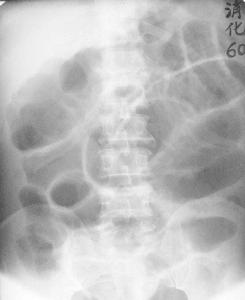

氣鋇雙重造影示回盲部1、X線檢查:腹部平片,可見擴張的腸管(梗阻病變近端腸管)。小腸造影:顯示鋇劑從吻合口逆行進入曠置的腸管,並且有一部分通過狹窄部位逆行進入曠置的近端腸管,然後再由順蠕動將鋇劑推入吻合口遠端,或逆蠕動到吻合部位;